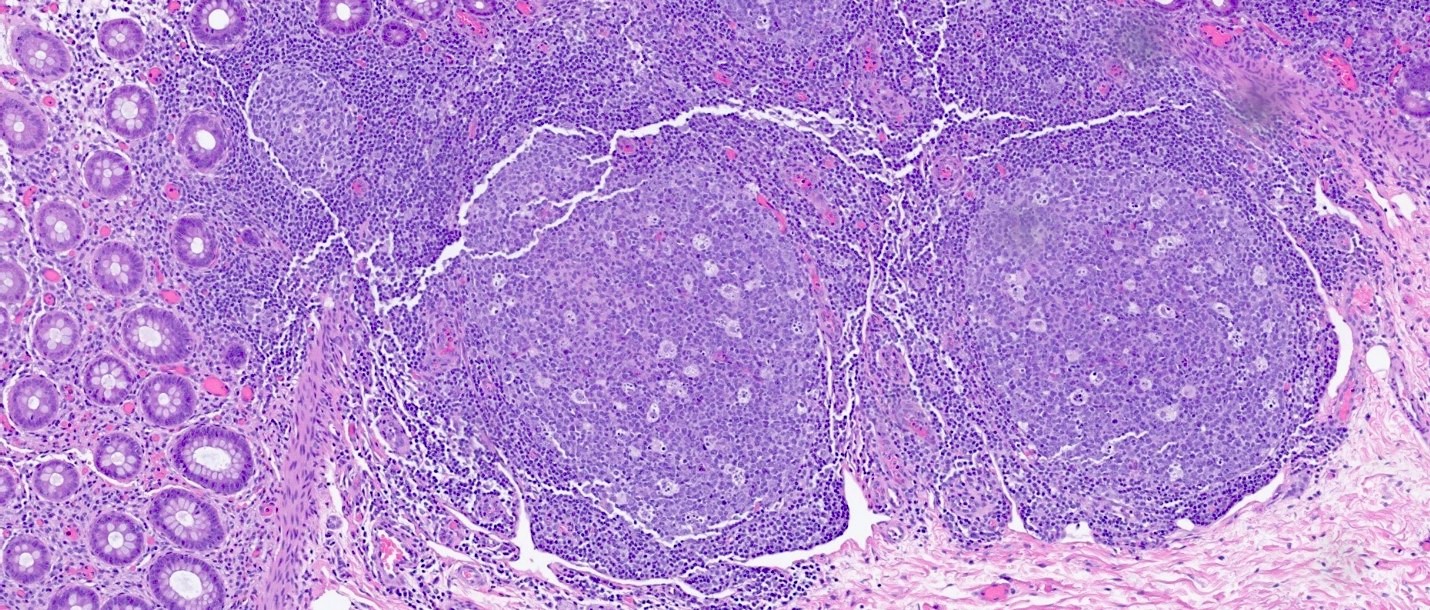

Microscopic (histologic) images

Contributed by Catherine E. Hagen, M.D. and Dustin W. Parsons, M.D.

Prominent lymphoid follicles Prominent lymphoid follicles Prominent lymphoid follicles

Prominent lymphoid follicles

Microscopic (histologic) description

• Lymphoid follicular hyperplasia with germinal centers

• Muscularis mucosa hypertrophy, which is often patchy

• Architectural changes with distortion of crypts, crypt branching and loss of crypts

• Degenerative mucosal surface epithelium with cell exfoliation and pyknotic nuclei

• Loss of goblet cells and mucin

• Mucosal ulceration with granulation tissue

• Varying degrees of inflammation, with features of both activity (neutrophil predominant) and chronicity (lymphoplasmacytic)

• Focal edema

• Pseudopolyps

• Paneth cell metaplasia

• References: Hum Pathol 2022;123:31, World J Gastroenterol 2018;24:1734, Histopathology 1991;19:55